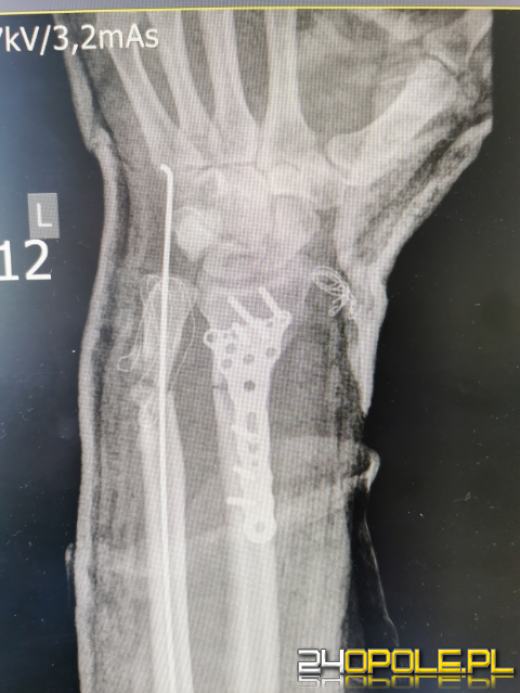

W wyniku pilnej interwencji chirurgicznej u 44-letniego Pacjenta w SP ZOZ w Kędzierzynie-Koźlu wykonano zespolenie struktur ręki prawie odciętej w lewym przedramieniu. Po przeprowadzonej 3 godzinnej trudnej operacji Pacjent zachował rękę. Nie było powikłań po zabiegu i po półtoratygodniowym pobycie w szpitalu został wypisany i wraca do zdrowia.

Późnym popołudniem w poniedziałek 19 lipca br. do naszego szpitala trafił 44-letni mężczyzna z prawie odciętą w przedramieniu lewą ręką (częściowa amputacja na poziomie 1/3 dystalnej przedramienia lewego). Rozległy uraz powstał w wyniku kontaktu z maszyną do mieszania betonu. Ze względu na zachowane ukrwienie kończyny (poprzez tętnicę łokciową) Pacjent nie został zakwalifikowany do leczenia przez zespół replantacyjny.

Z uwagi na rozległy uraz oraz inne okoliczności zdarzenia podjęliśmy natychmiastowe działania ratujące rękę Pacjenta. Zespół operacyjny pod kierunkiem dr Marcina Felsza dokonał zespolenia kości promieniowej (płytką LCP Hofer) oraz stabilizację złamania kości łokciowej (drutem Kirschnera). Połączono także ścięgna i pozostałe struktury ręki. Operacja trwała ok. 3 godzin.

- Pacjent urazu doznał w kontakcie z maszyną do produkcji betonu. Próbowaliśmy się skontaktować z oddziałami chirurgii ręki, ale one nie miały możliwości zaopatrzenia. Musieliśmy sobie poradzić sami. Przyjęliśmy Pacjenta do oddziału. Okazało się 4/5 obwodu zostało przecięte, po dokładniejszym zbadaniu była szansa że kończyna przeżyje. Zabieg wykonano w znieczuleniu ogólnym. Wykonaliśmy zabieg zespolenia kości i zeszyliśmy struktury miękkie, część ukrwienia została zachowana. Pacjent dobrze to zniósł, nie było zaburzeń ukrwienia. Nie było powikłań w okresie pooperacyjnym i Pacjent został wypisany do domu - powiedział dr Marcin Felsz - Kierownik Oddziału Urazowo-ortopedycznego.